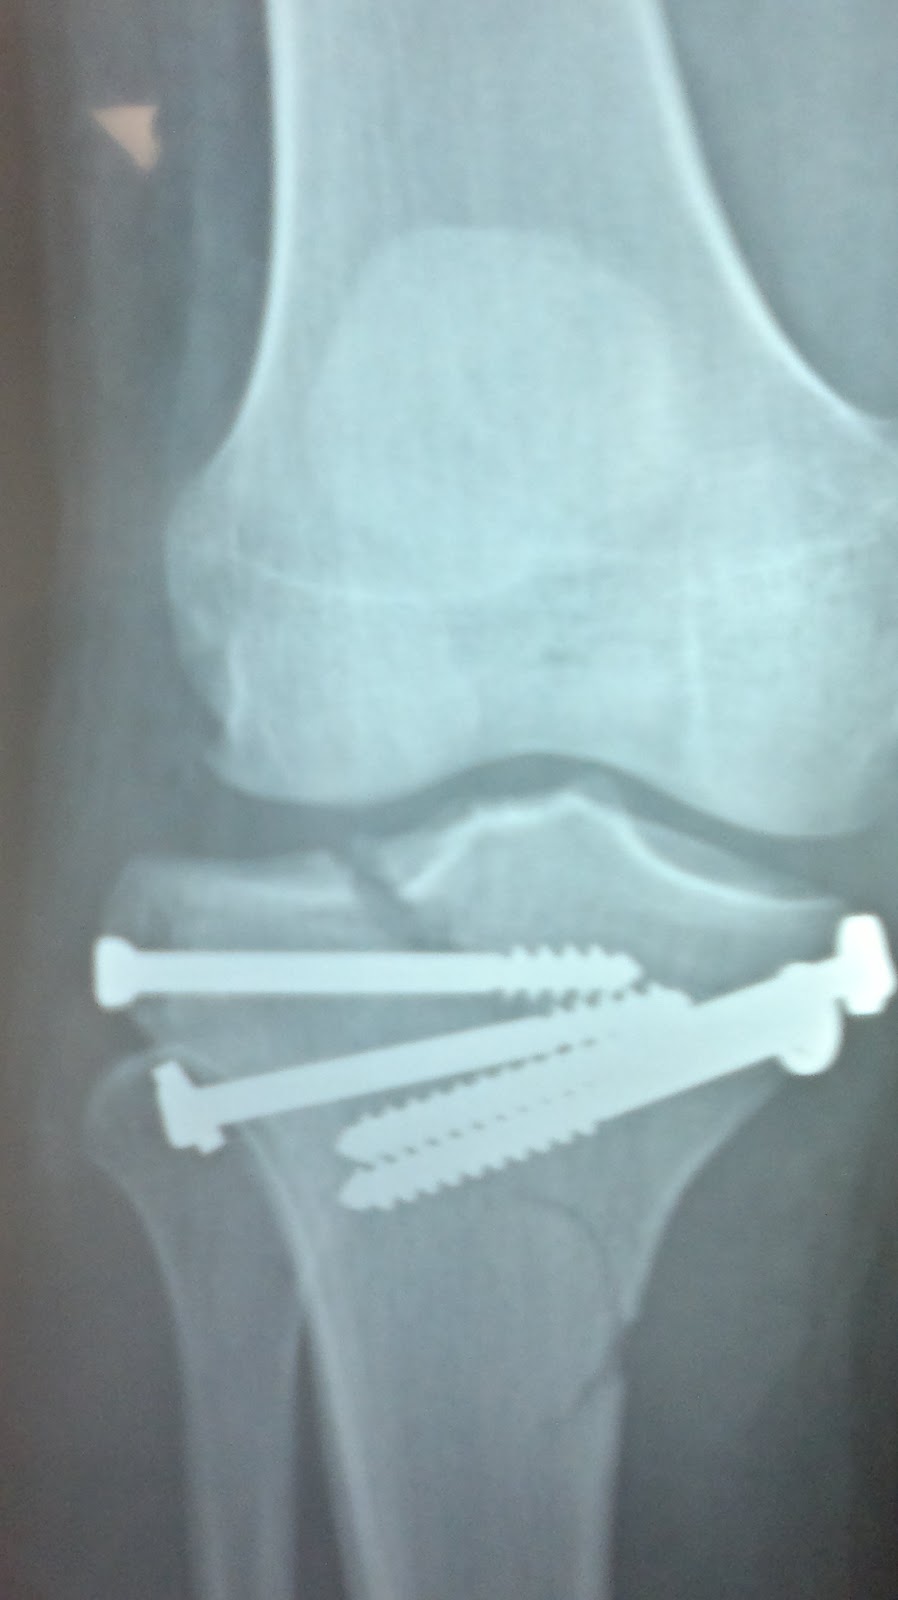

Varón 40 años. Fractura bituberositaria de meseta tibial. Radiografía anteroposterior. Osteosíntesis con placa de soporte, tornillos y cerclaje de alambre en la espina tibial.. que en los últimos años se viene usando con más asiduidad en apoyo de las técnicas de osteosíntesis en las fracturas de meseta tibial es la artroscopia 16-18. Clasificación de Moore. Tipo 1: por separación del platillo tibial medial en el plano coronal. Tipo 2: fractura completa del cóndilo, (el trazo de fractura comienza en el compartimento opuesto que se extiende a través de la eminencia tibial). Tipo 3: fractura marginal por avulsión. Tipo 4: fractura marginal, hundimiento del reborde.